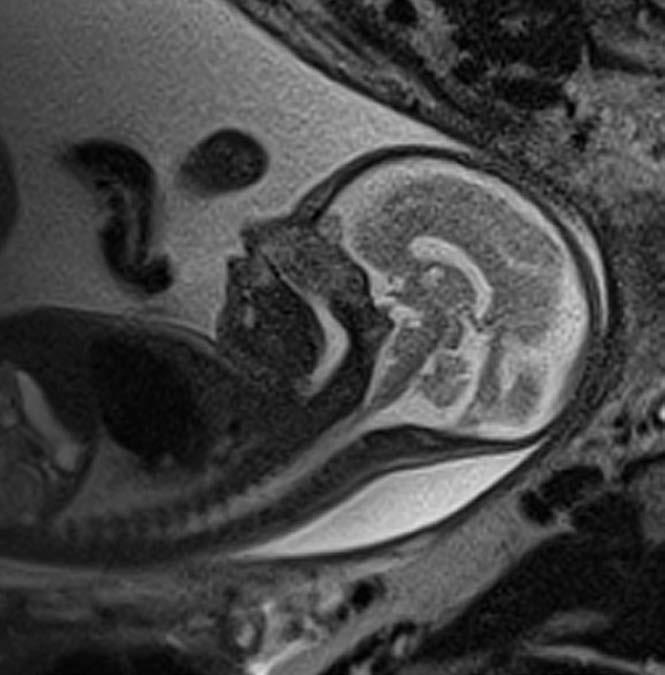

When an unborn baby has an abnormality, decisions about the delivery and neonatal care can often be planned in advance – with the help of an MRI.

MRI image acquisition can be tricky and quality reporting is an acquired skill. An expert in the field, Dr Lauren Raubenheimer honed her skills in London under world-renowned foetal and neonatal imaging specialist, Prof Mary Rutherford. Dr Raubenheimer joined SCP Radiology as a consulting radiologist.

“When a couple discovers their baby has an abnormality, the impact is enormous,” she explains. “I hope my findings give parents more answers as they navigate a difficult path.” With the help of an MRI, Dr Raubenheimer says that in many cases, the timing and route of delivery, as well as the neonatal care required, can be planned in advance.

Specialists after an abnormality has been detected on a screening ultrasound. An MRI can be done to confirm the abnormality, as well as to assess for abnormalities that are not readily visible through standard imaging techniques. This can significantly affect the prognosis. A foetal MRI can be performed either in the second or third trimester.

Dr Raubenheimer’s special interest is in developmental foetal brain abnormalities, but she also performs MRIs for body abnormalities, including congenital diaphragmatic hernia and spina bifida.

MRI can be superior to ultrasound in certain instances, such as assessing the folding of the brain and parts of the brain obscured by the skull, when amniotic fluid is low and when mothers have a high body mass index (BMI).

Foetal movement used to be an obstacle in getting good quality MR images. However, with today’s advanced magnets and faster imaging sequences, excellent image quality can be obtained. At SCP Radiology, foetal MRI scans are done exclusively by lead MRI radiographer Andrea Nagel.

Safety is, of course, of utmost importance. Dr Raubenheimer reassures us that present data shows no conclusively documented harmful effects of MRI imaging on the

developing foetus, providing it is at the safe and optimal level. She also adds that MRI does not use ionising radiation, and intravenous contrast is not administered in foetal MRI.

Foetal MRI is covered by medical aids, but pre-authorisation is required.

Dr Raubenheimer prefers that patients are referred from a Foetal Medicine Specialist after a detailed ultrasound. “Having access to ultrasound reports and knowing the exact gestation is crucial to an accurate MRI report,” she emphasises.